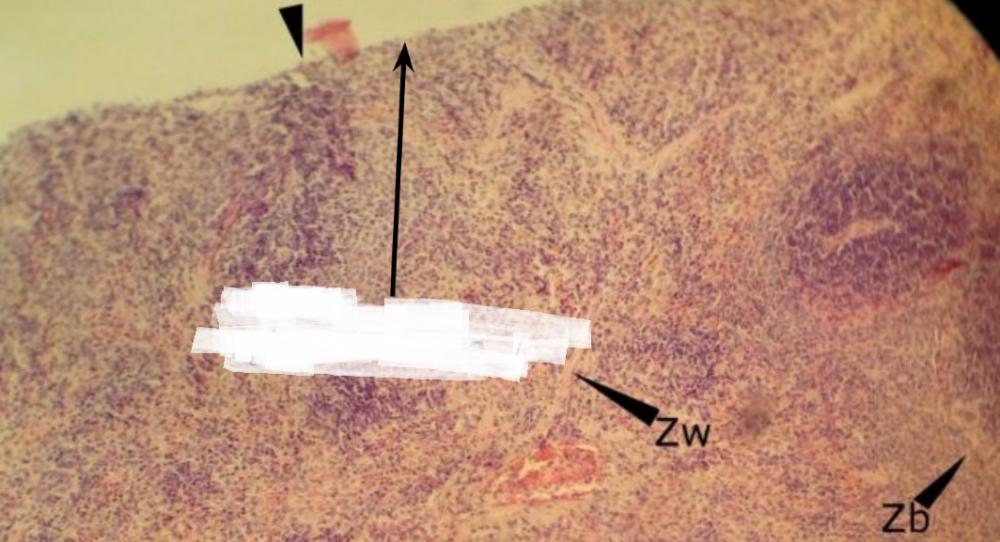

zatoka właściwa (śledziona)

Pytanie 115

nabłonek wielowarstwowy płaski (migdałek podniebienny)